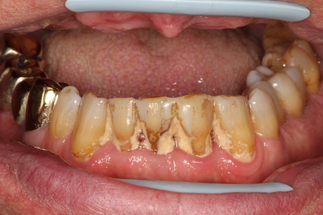

В основной группе 2 на фоне проводимого комплексного лечения с использованием геля «Метрогил-дента» отмечали улучшение как субъективных, так и объективных проявлений заболевания: уменьшались болезненность и кровоточивость десен, галитоз. Через 30 дней после лечения пациенты обеих групп отмечали значительное снижение болезненности, отека и кровоточивости десен, исчезновение неприятного запаха изо рта, некоторое снижение подвижности зубов, появление уверенности при жевании, улучшение общего состояния. При объективном обследовании отмечали уплотнение десневого края за счет уменьшения отека, существенное улучшение гигиенического состояния полости рта, прекращение выделения экссудата из пародонтальных карманов (Рисунок 13).

| до лечения | через 30 дней после лечения |

| Рисунок 13. Динамика состояния тканей пародонта у пациента с ХГП тяжелой степени через 30 дней после комплексного консервативного лечения с местным применением препарата «Метрогил-Дента» . | |